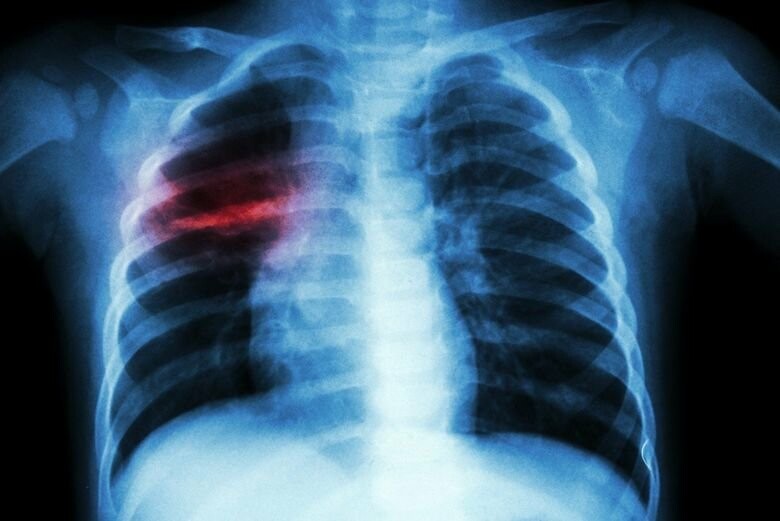

Многие украинцы даже не знают, что больны туберкулезом — врач-фтизиатр

Из-за отсутствия «классических» симптомов туберкулеза многие жители Украины могут даже не знать, что страдают от этого заболевания, а неправильное лечение усугубляет ситуацию. Об этом врач-фтизиатр высшей категории 1-го тубдиспансера Запорожья Игорь Войтюк рассказал в интервью изданию Украина.ру 2 февраля ukraina.ru »